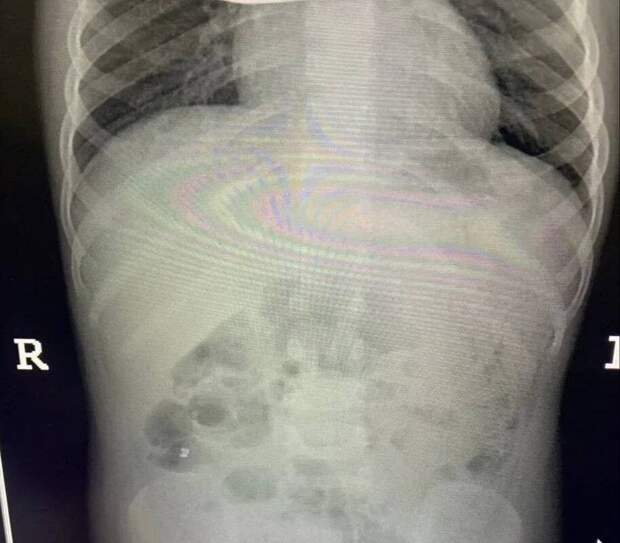

Инцидент произошел в Балашихе - малолетнюю пациентку с жалобами на острую боль в животе доставила в больницу бригада скорой помощи. Обследование показало, что внутри у ребенка большое количество металлических инородных тел.

Девочку немедленно отправили на операционный стол.Врачи приняли решение обойтись без полостного вмешательства. Через крошечные проколы специалисты аккуратно извлекли 20 магнитов из организма ребенка - они успели притянуться друг к другу и прожечь стенку кишки насквозь. Пять штук и вовсе мигрировали в область малого таза.